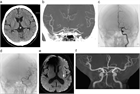

1. 脳卒中の初発症候の多くは片麻痺である。片麻痺が突然発症した場合、脳卒中発症を第一に考えて検査、治療を勧めるのが妥当である(推奨度2)

1. 片麻痺が突然発症し、脳CT検査を施行し脳出血が除外されれば、脳梗塞急性期と判断し発症後4.5時間以内であれば適用基準を遵守して血栓溶解薬(アルテプラーゼ)を投与することが推奨される(推奨度1)。また発症6時間以内の脳主幹動脈閉塞症例ではアルテプラーゼ静注療法を含む内科治療に追加して機械的血栓回収療法を開始することが推奨される(推奨度1)。いずれも治療開始が早いほど治療効果は大きいため、迅速に実施する(推奨度1)。発症6時間以後の脳主幹動脈閉塞症例では神経徴候と画像診断に基づく治療適応判定を行い16時間以内に血栓回収療法を開始することが勧められる(推奨度1)。また16~24時間以内に同療法を開始することは妥当である(推奨度2)

1. 片麻痺を数分以上生じた一過性脳虚血発作の患者には、すみやかに脳MRI検査(拡散強調画像)を施行することが勧められる(推奨度1)。脳MRI検査をすみやかに実施できない場合でも、少なくとも脳CT検査を試行して脳出血を除外したうえで抗血栓治療を開始し、可及的早期に脳MRI検査を実施する(推奨度1)